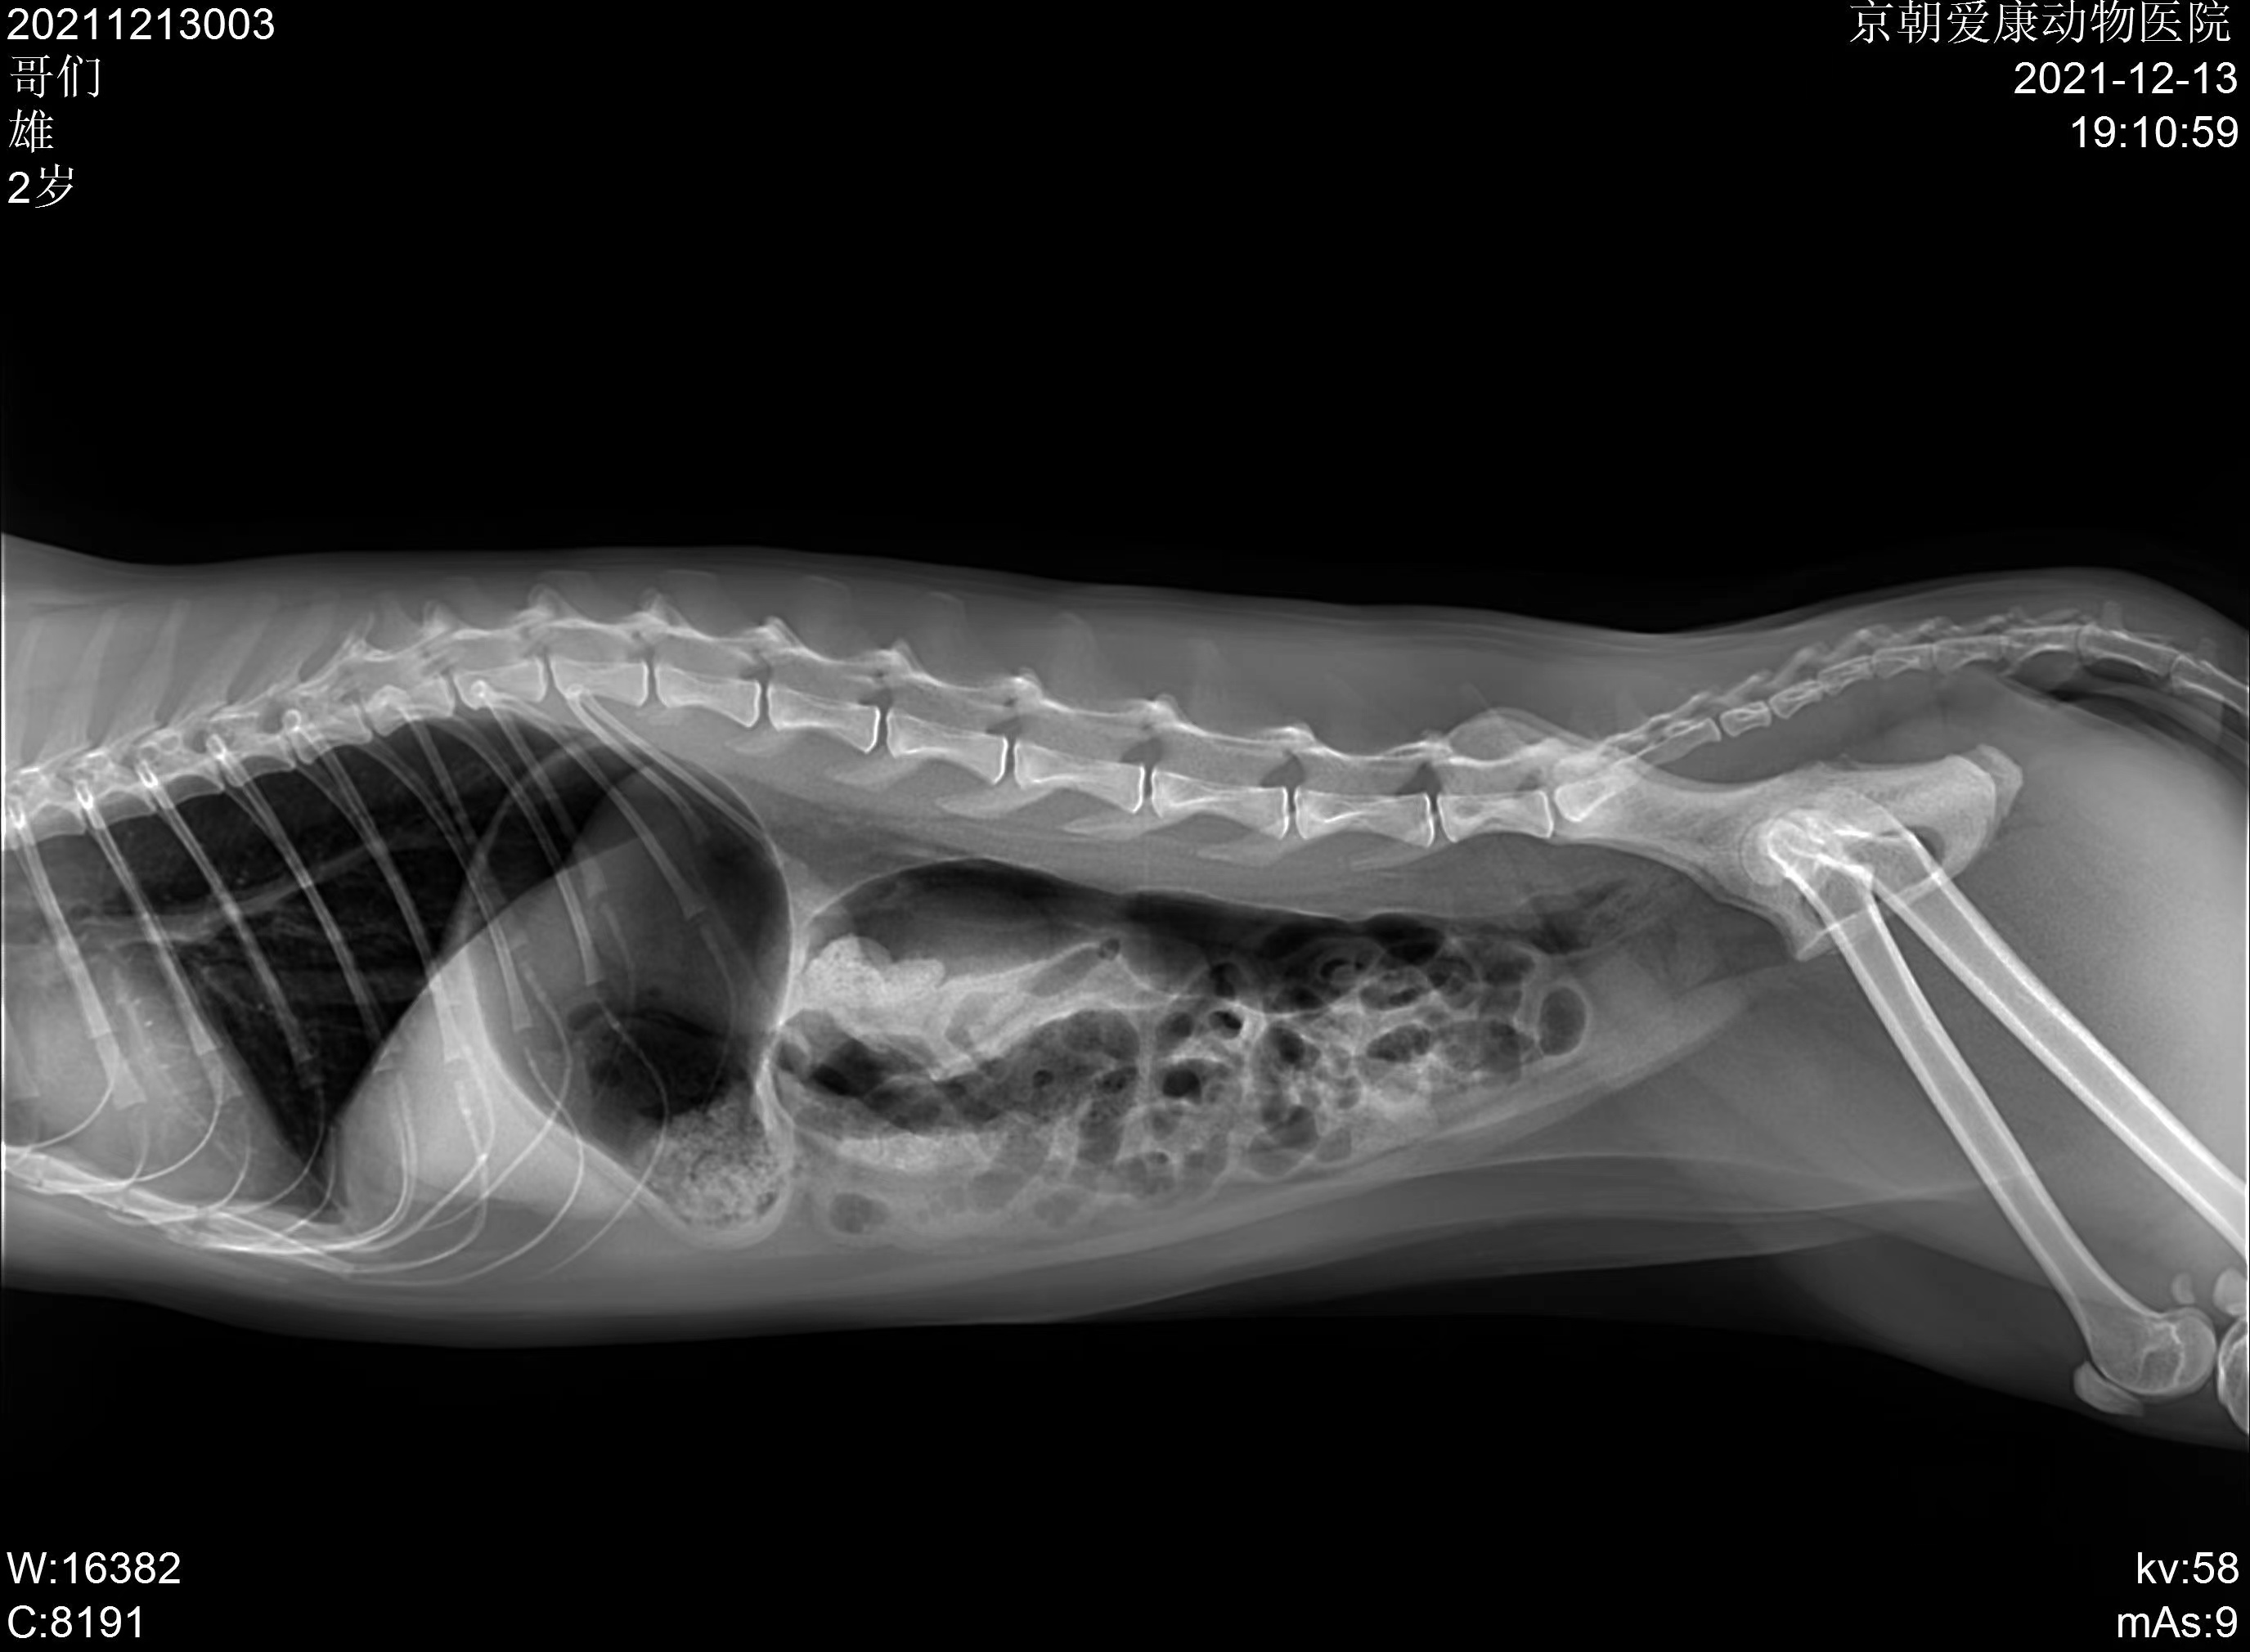

“灵魂吸入”的深渊高贵混血王子→ 哥们儿

【我们这期的封面就是这位宝贝~】

【阿花的深渊哥们儿的屎蛋儿🤣( ̄︶ ̄)↗ 】